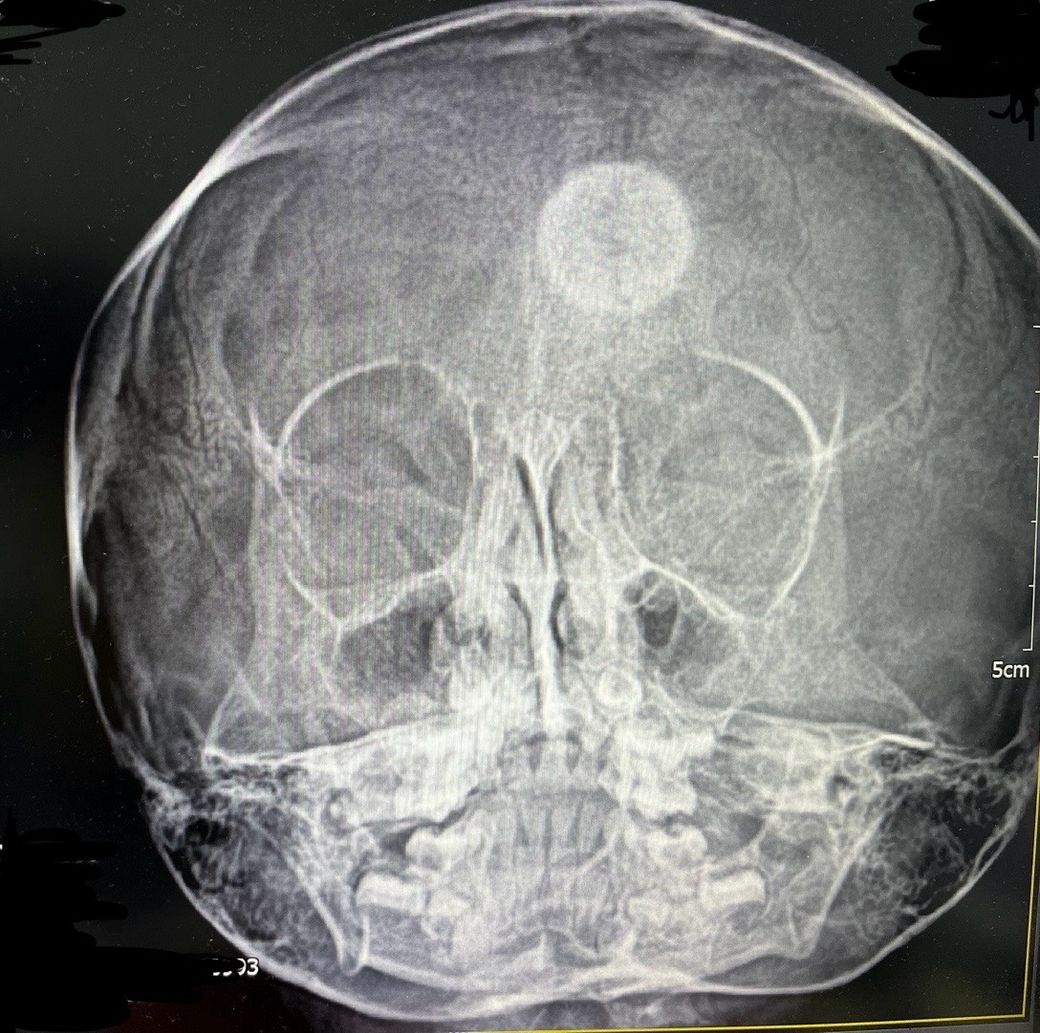

5세 여아입니다 얼마전 부비동 엑스레이사진 입니다

머리에 흰색 원이 보이는데요

소아과 원장님도 처음 보는거라시네요

무엇일까요?

부비동 엑스레이에서 머리에 흰색 원이 보인다는 것은 확실히 걱정스러운 일일 수 있습니다. 일반적으로 엑스레이에서 흰색 원이 보이는 것은 기타 이상이나 특이한 문제를 의심해 볼 수 있습니다.

의심해 볼 수 있는 문제로는 부비동에 농이 차서 엑스레이에서 흰색으로 나타날 수 있습니다. 하지만 보통 이 경우에는 다른 증상도 동반됩니다.

혹은 엑스레이에서는 종양, 결절, 또는 다른 비정상적인 조직이 나타날 수도 있고, 부비동 외에도 두개골에서의 변형이나 이상이 엑스레이에 나타날 수 있습니다.

• 엑스레이 사진만 놓고 구체적으로 무엇인지 판단 내리기는 어렵습니다. 원형의 이물질 같은 것이 보이는데 촬영 상 우연히 기계의 이상이 발생하거나 한 것이 아니라면 일단 분명 이상 소견이라고 판단을 하여야 하겠습니다. 관련하여서는 CT 등의 보다 정밀한 검사를 통하여 더 자세하게 어떠한 것인지 파악해보는 것이 필요할 것으로 사료됩니다. 현재로서는 신경외과로 가셔서 정밀하게 파악해보는 것을 권고드립니다.